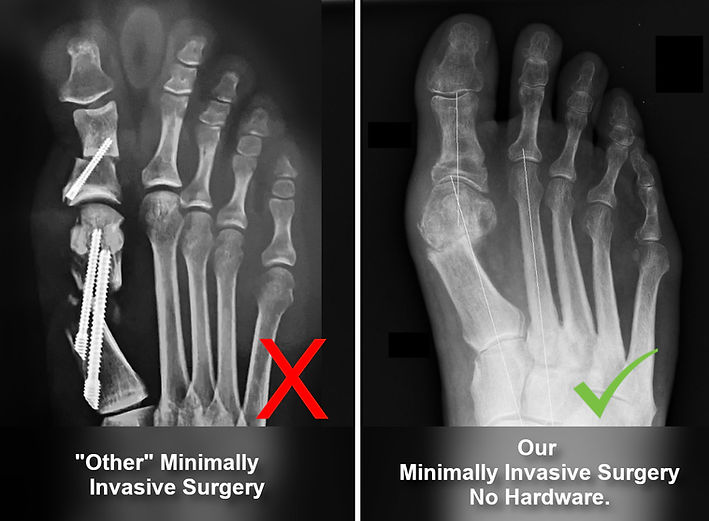

We don't leave permanent painful hardware in your foot.

Superior Cosmetic Result!

No large incisions or scars!

- we do this without permanent screws, plates, or large incisions!

The Problem with

Traditional Foot Surgery

The image below speaks volumes. Foot surgery is known for its pain and debilitation due to the use of large orthopedic hardware, heavy anesthesia for significant incisions, and painful metal implants. This leads to extended downtimes, preventing walking and affecting family and job responsibilities, often requiring narcotics for pain relief. But it doesn't have to be this way. Keep reading.